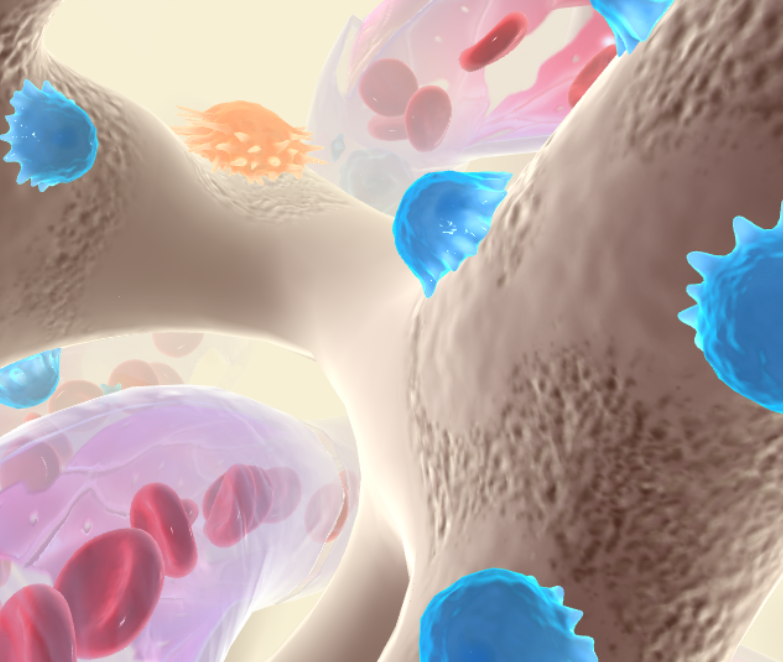

Osteoblasts

A bone-forming cell

Osteoclasts

Any of the large multinucleate cells closely associated with areas of bone resportion (such as in a fracture that is

What do osteoblasts and osteoclasts do together?

Help maintain a balance of building new bone and breaking down old or damaged tissue

What are the blue figures?

What are the orange figures?